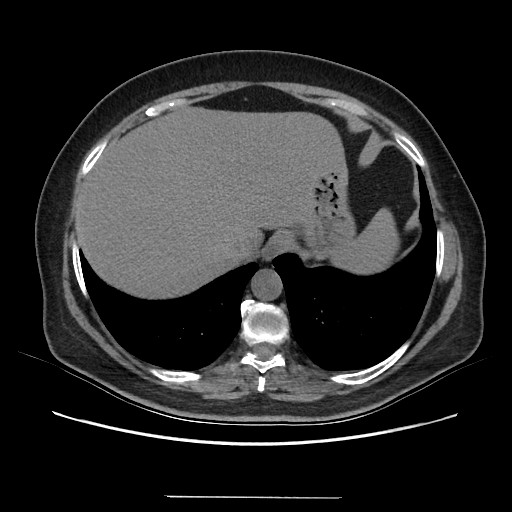

Generated VENOUS CT scan (A→B translation)

Full window (WL 1023.5, WW 4095 β†’ Low βˆ’1024, High +3071)

Actual HU range: [-1024.0, 838.3]